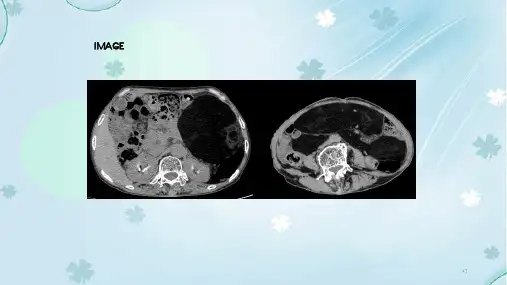

超声检查(图1A 、B )提示:肝内混合性占位;考虑为恶性病变。

超声造影(图1C 、D )提示:肝恶性病变可能性大(肉瘤?)。

腹部增强CT 提示:肝内较大类圆形低密度影,增强扫描动脉期病变内可见多发血管影,随时间延长病变内强化范围增大,其内可见斑片状无强化低密度影;考虑肝内恶性病变可能性大,不除外肉瘤。

图1 男,52岁,肝脏去分化脂肪肉瘤。

二维超声示肝内可见一大小约193 mm×172 mm×161 mm 的混合回声团,边界尚清,内部回声欠均匀,可见小片状无回声区(A );彩色多普勒血流显像示混合回声团内可见短棒状血流信号(B );超声造影动脉相示病灶周边呈细环状增强,中心呈不均匀高增强,呈火焰征,内可见多发不规则无增强区(C );超声造影门静脉相示病灶呈不均匀等增强(D );病理示高级别肉瘤(HE ,×200,E )2 讨论脂肪肉瘤是常见的软组织恶性肿瘤之一,起源于人体原始间充质细胞[1],好发于腹膜后、盆腔及四肢等部位。